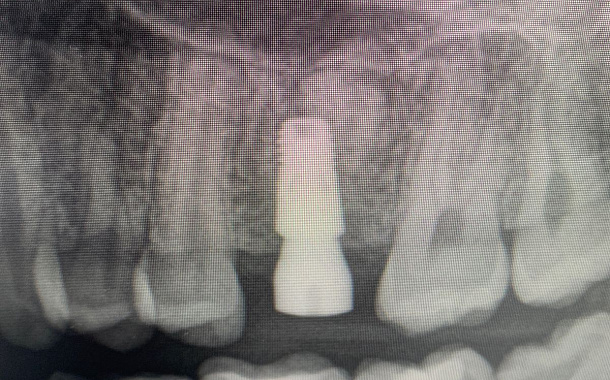

- Установка имплантата в запланированном положении, заполнение пространства лунки костно-пластическим материалом, наложение швов.

- Установка временной ортопедической конструкции.

Врач решает это в ходе обследования, а в некоторых случаях и в ходе операции. В случае получения необходимой первичной стабильности зубного импланта (т.е. усилие с которым была проведена установка имплантата в кость), в день операции фиксируется временная ортопедическая конструкция.

Если по разным причинам в ходе установки не удалось достигнуть необходимой для немедленной нагрузки первичной стабильности имплантата, проводится установка индивидуального формирователя десны и отсроченное протезирование через 4-6 месяцев. В этом случае косметический или функциональный дефект восстанавливается частично-съемным протезом или несъемным временным протезом изготовленным ранее лабораторным способом или непосредственно в кресле после проведенной операции. Вариантом выбора может быть адгезивный мостовидный протез из композитного пломбировочного материала.